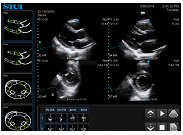

Cardiología

Un kit completo para el diagnóstico cardíaco, que incluye CW, TDI, modo anatómico M y modo color M, permite los exámenes de emergencia. Una variedad de mediciones ofrece soluciones prácticas, como PISA, auto rastreo de Simpson, volúmenes cardíacos del VI, etc.